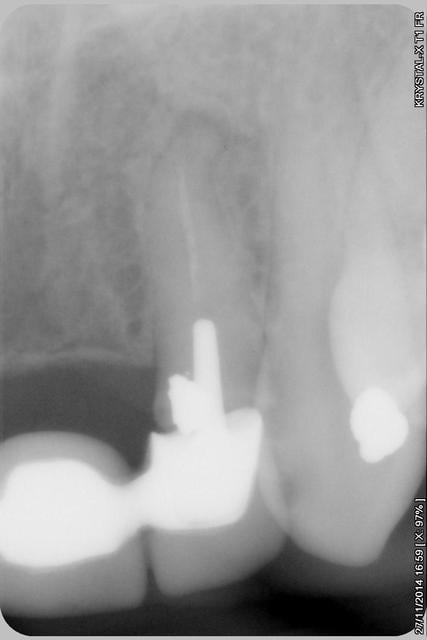

Les endo et les IC dans les 12-22 sont sublimes...et ça a durer 10 ans....incroyable...Il y a pas de la paro aussi ?

étonnant en effet... et encore plus étonnant, ce qui n'arrive jamais le radiologue (qui est parfaitement compétent normalement) a inversé la droite et la gauche.

le scan n'est pas terrible, mais suffisant pour voir que 22 une fois extraite, ne va pas etre simple à implanter, par contre 11/21 avec un peu d'expansion...

Donc dans un premier temps,je décide d'essayer de retraiter 12/22, de toute façons ça ne peut pas être pire que ce qui tiens depuis 10 ans... enfin 12 mobilité quasiment 3.

Sur la reprise de 22 je pense que tu as fais un beau "tout-droit" à l'apex... le canal devait suivre la courbure.

je pense que le tout droit existait déjà..